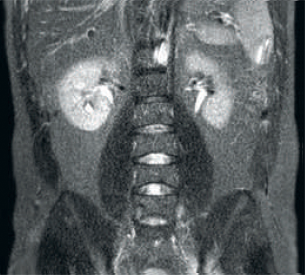

結果:同じスキャンパラメータでノイズの多い画像

dStream RF受信技術により、MR信号をRFコイル内で直接デジタル変換できます。これにより、画像ボリューム全体にわたってSNRが最大40%向上¹しました。

Hennepin County Medical Center(HCMC)では、dStream技術を搭載するMR装置Ingenia 1.5Tを運用しています。*

* 非デジタル/dStreamシステムのAchievaと比較して信号対雑音比が最大40%向上しました。